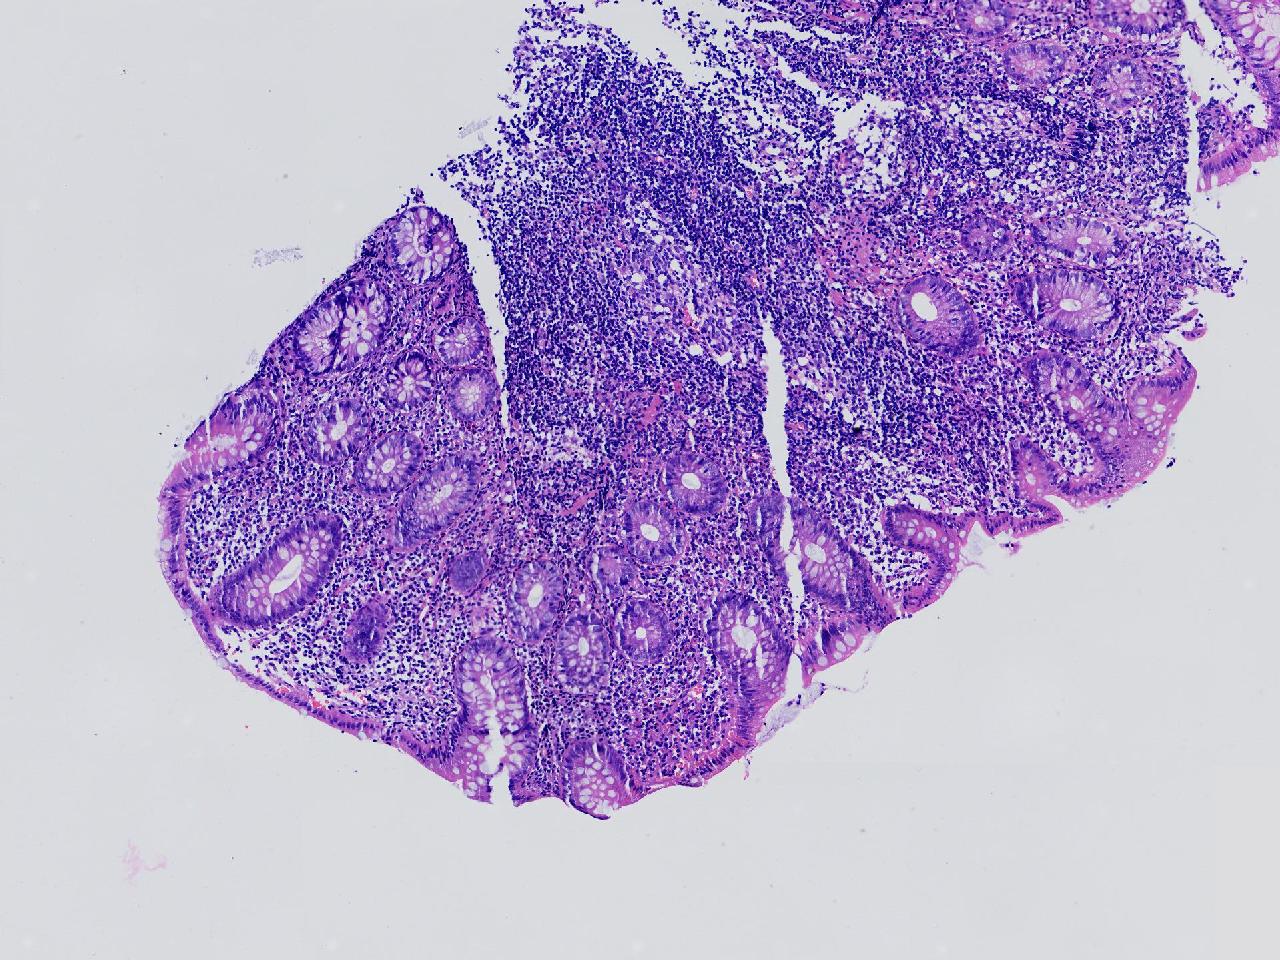

男,62岁,回盲部附近见多发片状溃疡,底覆薄白苔,周围粘膜充血水肿,活检2块,质软,弹性可。

回盲部活检

灰白色不整形软组织2块,直径均0.2厘米。

考虑:溃疡性结肠炎?

炎症性肠病要考虑,具体的类型不太好确定,需要结合临床。

上级医院会诊,不除外炎症性肠病,结合临床。